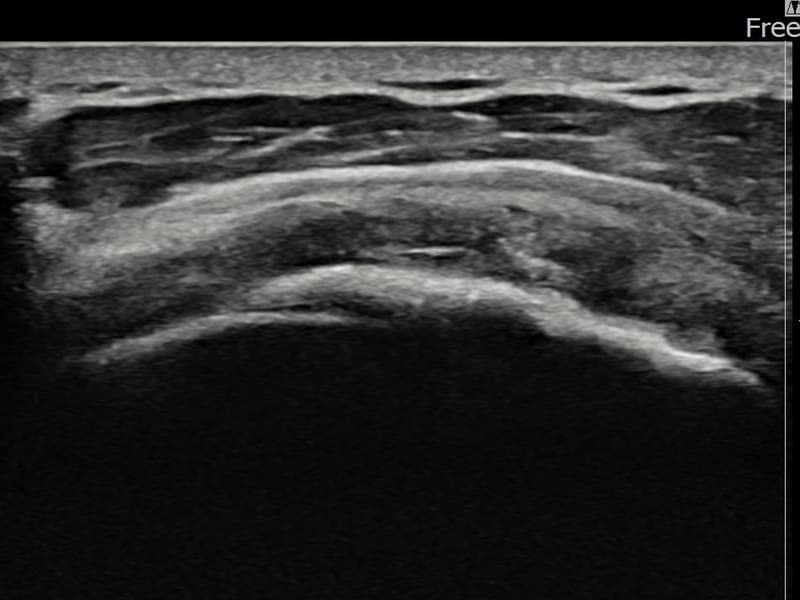

After

시술 전 초음파 측정 결과 파열 크기는 15mm × 6mm (힘줄 두께의 약 70% 결손)로 확인되었습니다. 시술 전 초음파에서 좌측 극상근건 전층에 걸친 광범위한 에코 단절과 심각한 힘줄 두께 감소가 확인되었습니다. 시술 후 초음파에서 광범위 파열 부위에 재생 조직이 형성되고 힘줄 연속성이 안정적으로 회복된 것이 관찰되었습니다.

50대 중반 남성 환자분으로, 좌측 어깨 광범위 파열로 타 병원에서 수술을 권유받으셨으나 비수술 치료를 원하셔서 내원하셨습니다. 팔을 들어 올리는 것 자체가 매우 힘들고 야간 통증이 극심한 상태였습니다. 정밀 초음파 검사에서 좌측 극상근건의 광범위 부분파열이 확인되었으며, 힘줄 두께가 현저히 감소된 상태였습니다. 파열 범위가 넓어 일반적인 주사 치료로는 회복이 어렵다고 판단하여 초음파 유도 하 축소봉합술을 시행하였습니다. 시술 후 보조기 착용 6주와 단계적 재활 운동을 통해 회복을 진행하였고, 시술 5주 후 추적 초음파에서 광범위 파열 부위의 구조적 안정화와 힘줄 연속성 회복이 확인되었습니다.